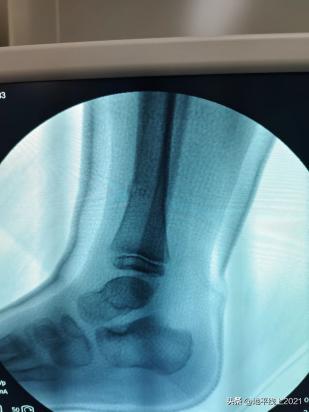

再看一个下肢的案例,同样是在麻醉下纠正,用一个管型树脂石膏固定。